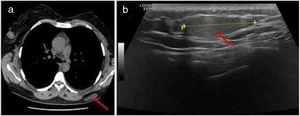

Imagiological features of the tumor: A, High-resolution thoracic computed tomography revealing a large, low-density, subcutaneous nodule in the left dorsal region (red arrow); B, Ultrasound revealing a well-defined, slightly hyperechoic, subcutaneous mass in the left dorsal region (red arrow).

A high-resolution thoracic computed tomography performed one year before, in the context of an episode of asthma exacerbation, had revealed a large, low-density, subcutaneous nodularity in the referred topography (Fig. 1A). Also, an ultrasound-guided core needle biopsy (Fig. 1B)of this well-defined, slightly hyperechoic, subcutaneous mass identified a neoplasm of globular cells, some with multi-vacuolated cytoplasm and others with granular, eosinophilic cytoplasm, without nuclear atypia.